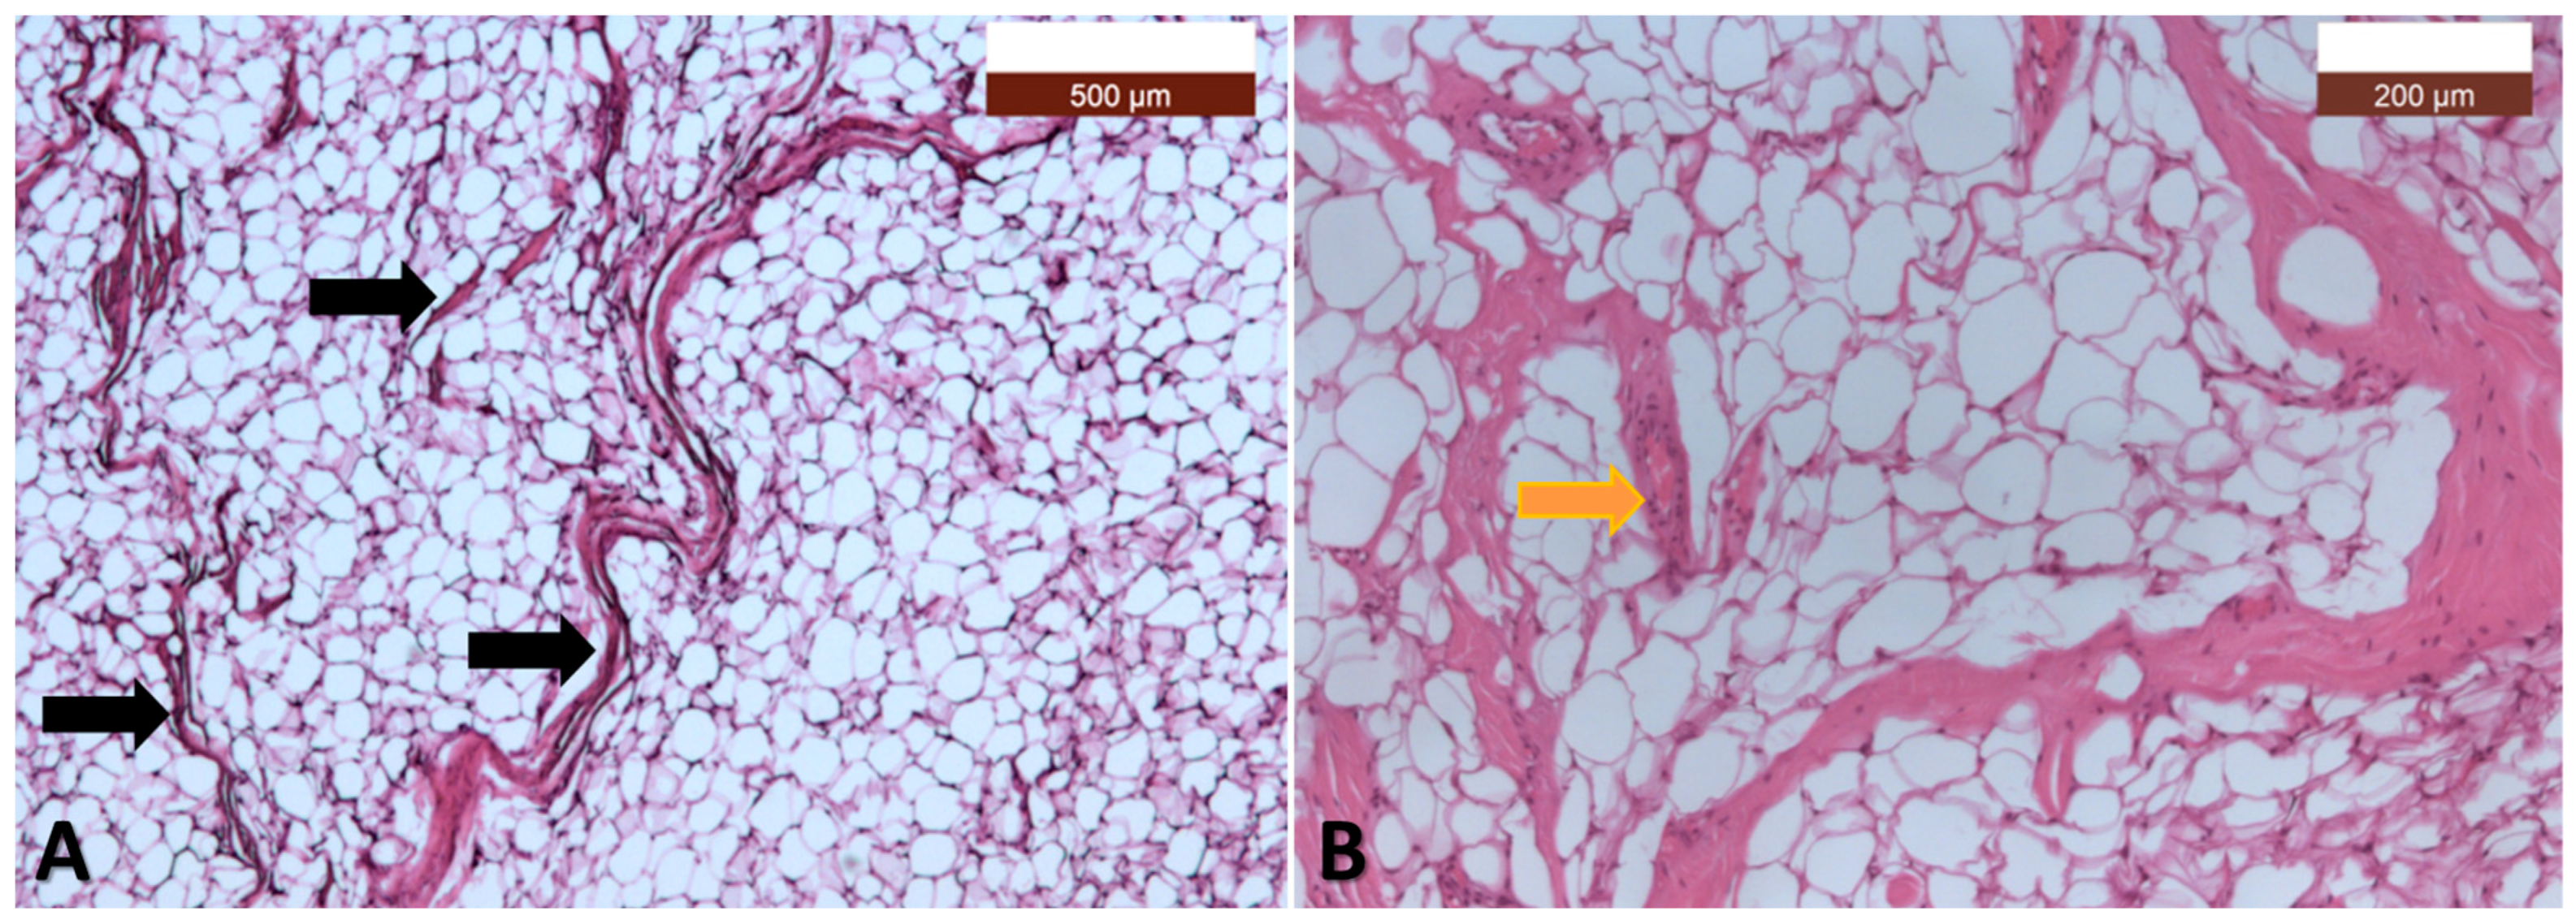

3.2. Pathology